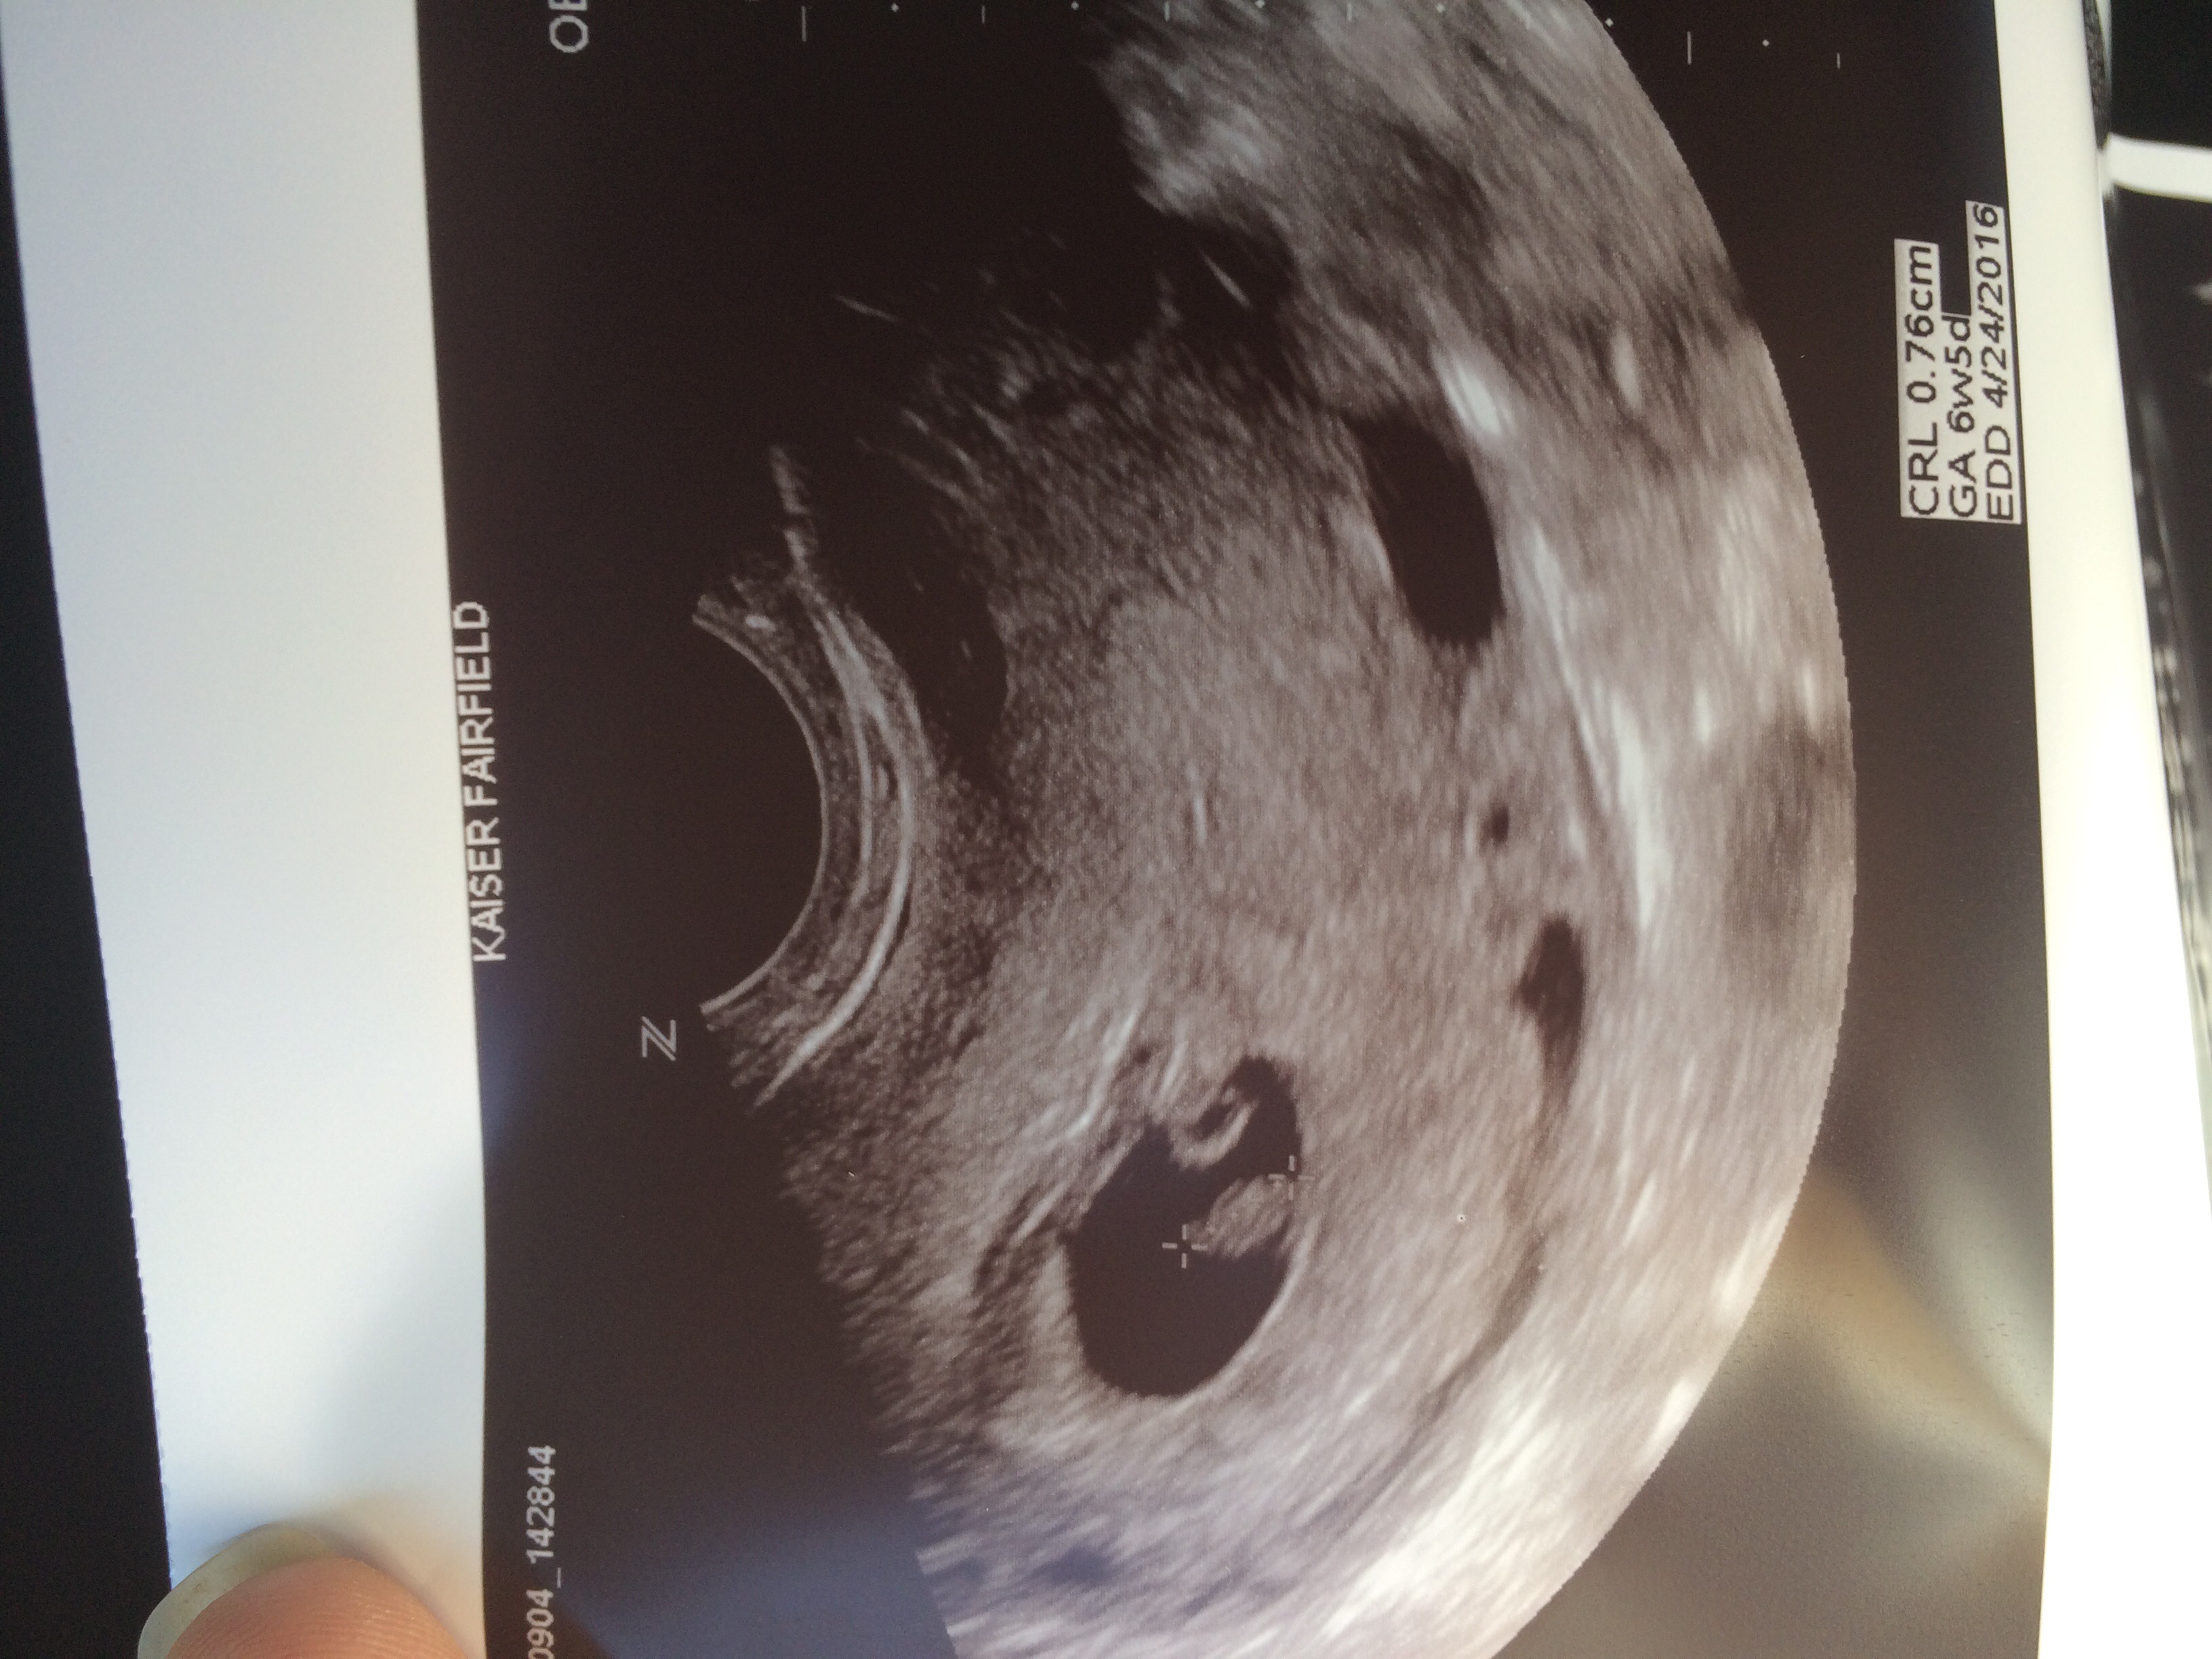

10 weeks and 2 days:) BMP was 175 it was AMAZING to see our little peanut dancing around. Very active!! This was our first ultra sound and it was spectacular:)